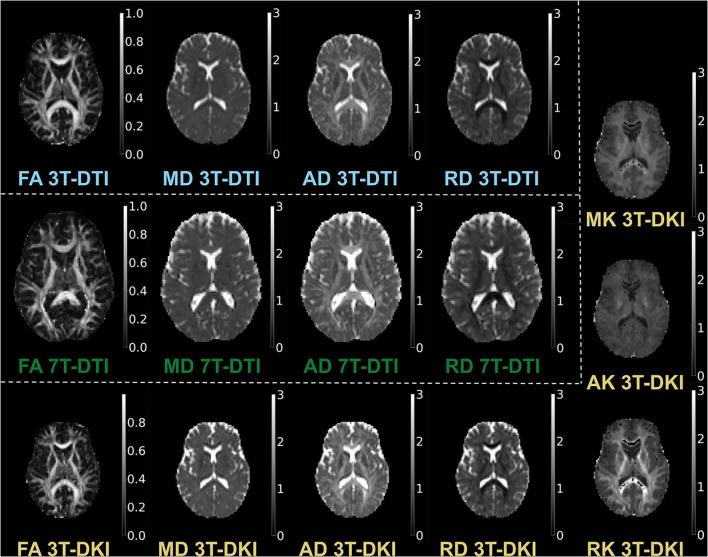

There are many ways to acquire and process diffusion MRI (dMRI) data for group studies, but it is unknown which maximizes the sensitivity to white matter (WM) pathology. Inspired by this question, we analyzed data acquired for diffusion tensor imaging (DTI) and diffusion kurtosis imaging (DKI) at 3T (3T-DTI and 3T-DKI) and DTI at 7T in patients with systemic lupus erythematosus (SLE) and healthy controls (HC). Parameter estimates in 72 WM tracts were obtained using TractSeg. The impact on the sensitivity to WM pathology was evaluated for the diffusion protocol, the magnetic field strength, and the processing pipeline. Sensitivity was quantified in terms of Cohen's for group comparison. Results showed that the choice of diffusion protocol had the largest impact on the effect size. The effect size in fractional anisotropy (FA) across all WM tracts was 0.26 higher when derived by DTI than by DKI and 0.20 higher in 3T compared with 7T. The difference due to the diffusion protocol was larger than the difference due to magnetic field strength for the majority of diffusion parameters. In contrast, the difference between including or excluding different processing steps was near negligible, except for the correction of distortions from eddy currents and motion which had a clearly positive impact. For example, effect sizes increased on average by 0.07 by including motion and eddy correction for FA derived from 3T-DTI. Effect sizes were slightly reduced by the incorporation of denoising and Gibbs-ringing removal (on average by 0.011 and 0.005, respectively). Smoothing prior to diffusion model fitting generally reduced effect sizes. In summary, 3T-DTI in combination with eddy current and motion correction yielded the highest sensitivity to WM pathology in patients with SLE. However, our results also indicated that the 3T-DKI and 7T-DTI protocols used here may be adjusted to increase effect sizes.

在群体研究中,有多种获取和处理扩散磁共振成像(dMRI)数据的方法,但尚不清楚哪种方法能最大程度地提高对白质(WM)病变的敏感性。受此问题启发,我们分析了系统性红斑狼疮(SLE)患者和健康对照(HC)在3T时进行扩散张量成像(DTI)和扩散峰度成像(DKI)(3T-DTI和3T-DKI)以及在7T时进行DTI所采集的数据。使用TractSeg获得了72条WM束的参数估计值。针对扩散协议、磁场强度和处理流程,评估了其对WM病变敏感性的影响。敏感性通过Cohen's 进行量化以用于组间比较。结果表明,扩散协议的选择对效应大小的影响最大。与DKI相比,通过DTI得出的所有WM束的分数各向异性(FA)效应大小高0.26,与7T相比,在3T时高0.20。对于大多数扩散参数而言,扩散协议造成的差异大于磁场强度造成的差异。相比之下,包含或排除不同处理步骤之间的差异几乎可以忽略不计,除了对涡流和运动引起的畸变进行校正有明显的积极影响。例如,对于3T-DTI得出的FA,通过纳入运动和涡流校正,效应大小平均增加了0.07。纳入去噪和吉布斯环去除后,效应大小略有降低(分别平均降低0.011和0.005)。在扩散模型拟合之前进行平滑处理通常会降低效应大小。总之,3T-DTI结合涡流和运动校正对SLE患者的WM病变具有最高的敏感性。然而,我们的结果还表明,此处使用的3T-DKI和7T-DTI协议可能需要调整以增加效应大小。